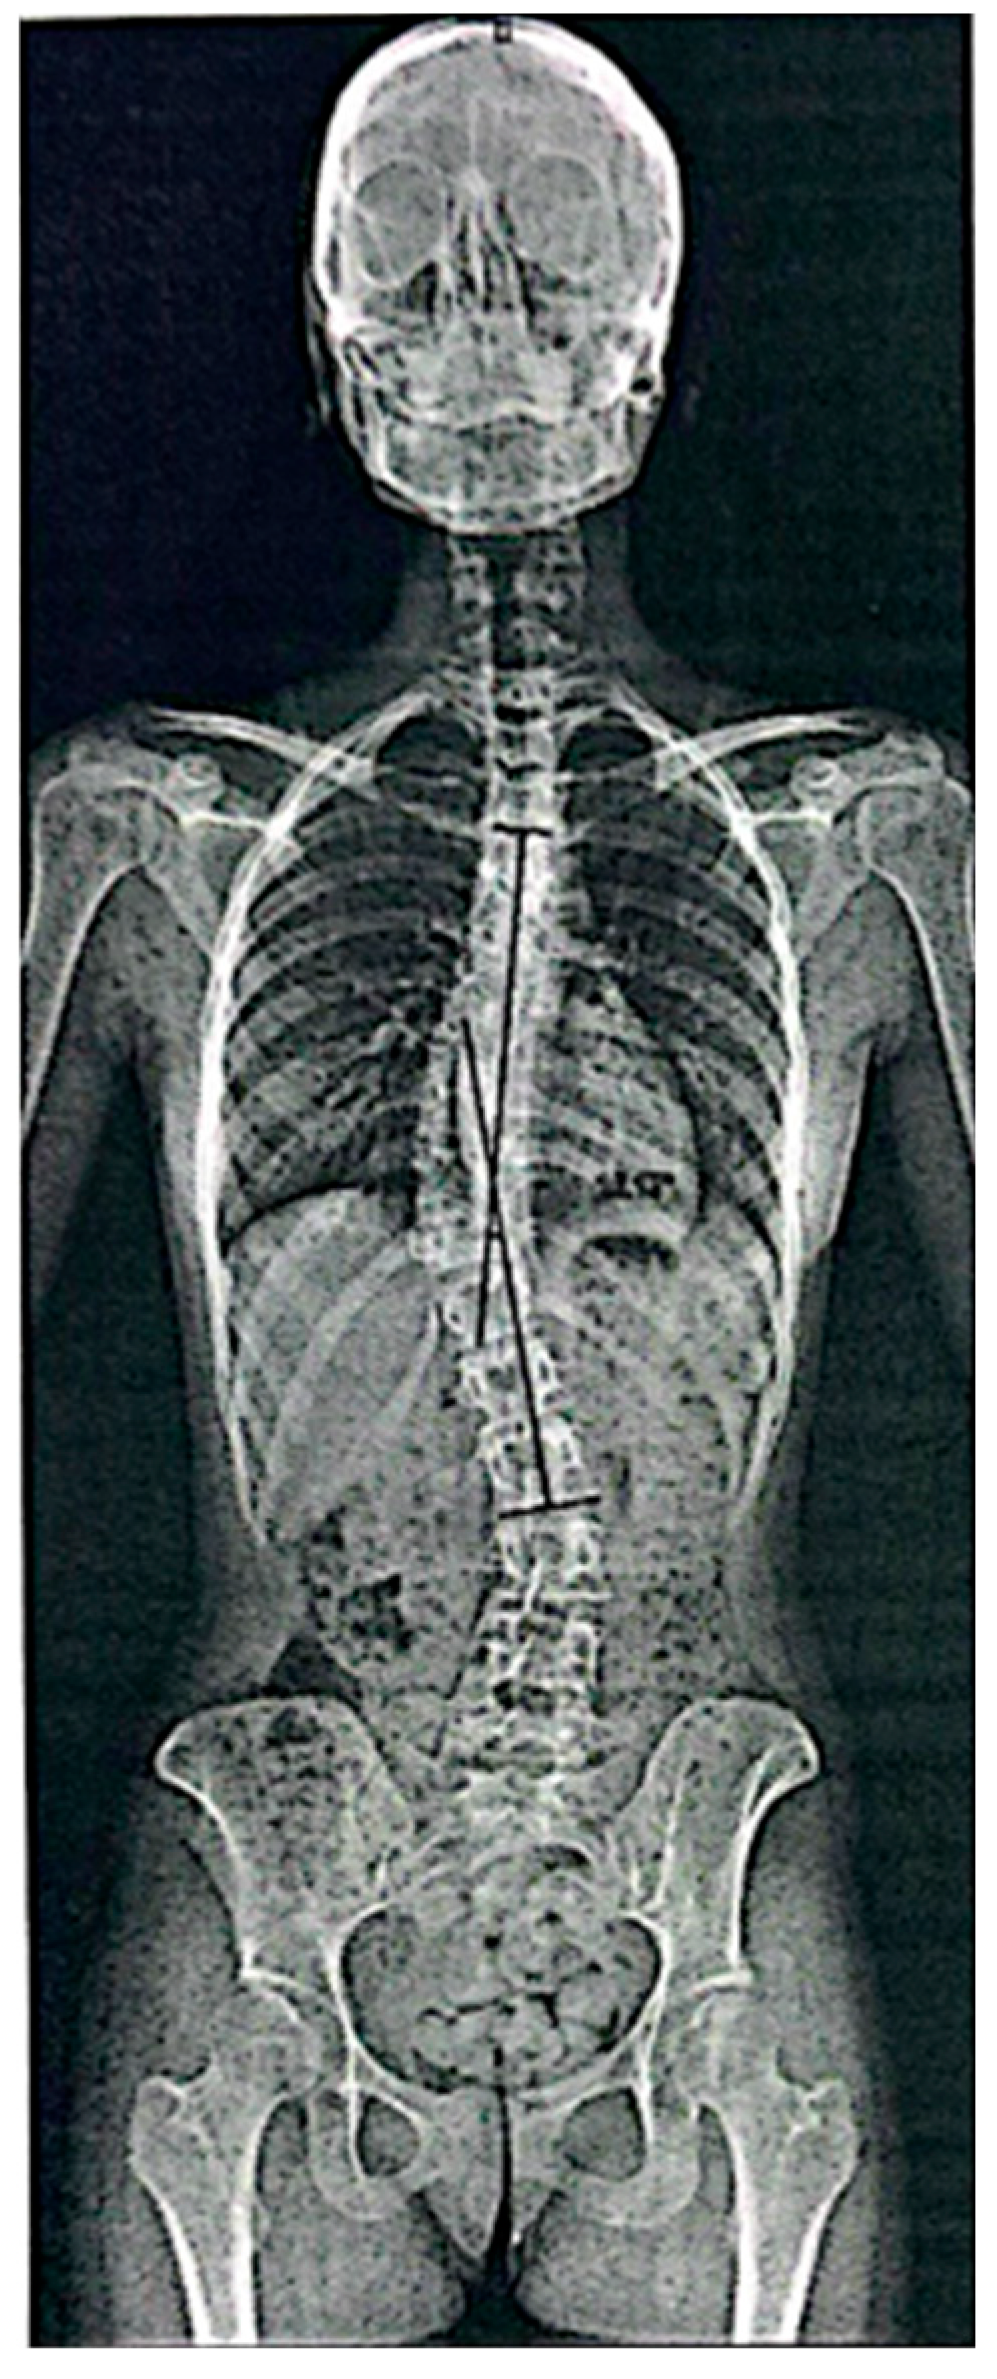

Standing spinal radiographs revealed right-convex thoracolumbar rotoscoliosis with the curved apex located between T10. The initial Cobb angle was 41.14°, consistent with moderate-to-severe scoliosis. Vertebral rotation was present, with a derotation angle ratio (DAR) of 3.7 (Figure 2).

Radiological evaluation also highlighted an asymmetry of pelvic alignment and vertebral straightening, with loss of the physiological curves of dorsal kyphosis and lumbar lordosis. Skeletal maturity was assessed as Risser grade 4, indicating an advanced stage of skeletal development and a lower likelihood of spontaneous curve correction.

Overall, the findings were consistent with thoracolumbar AIS in an advanced stage of skeletal maturity.

At baseline, Case 2 presented with a right-convex thoracolumbar curve with an apex at T10. The Cobb angle was 41.14°, with a DAR of 3.7, consistent with a moderate-to-severe curve and relevant rotational involvement. Pelvic asymmetry was also documented.

Figure 2. Case 2: Basic standing anteroposterior spinal X-ray showing right-convex thoracolumbar scoliosis (Cobb angle 41.14°). Black lines indicate Cobb angle measurement performed by the radiologist between the upper and lower end vertebrae of the curve.